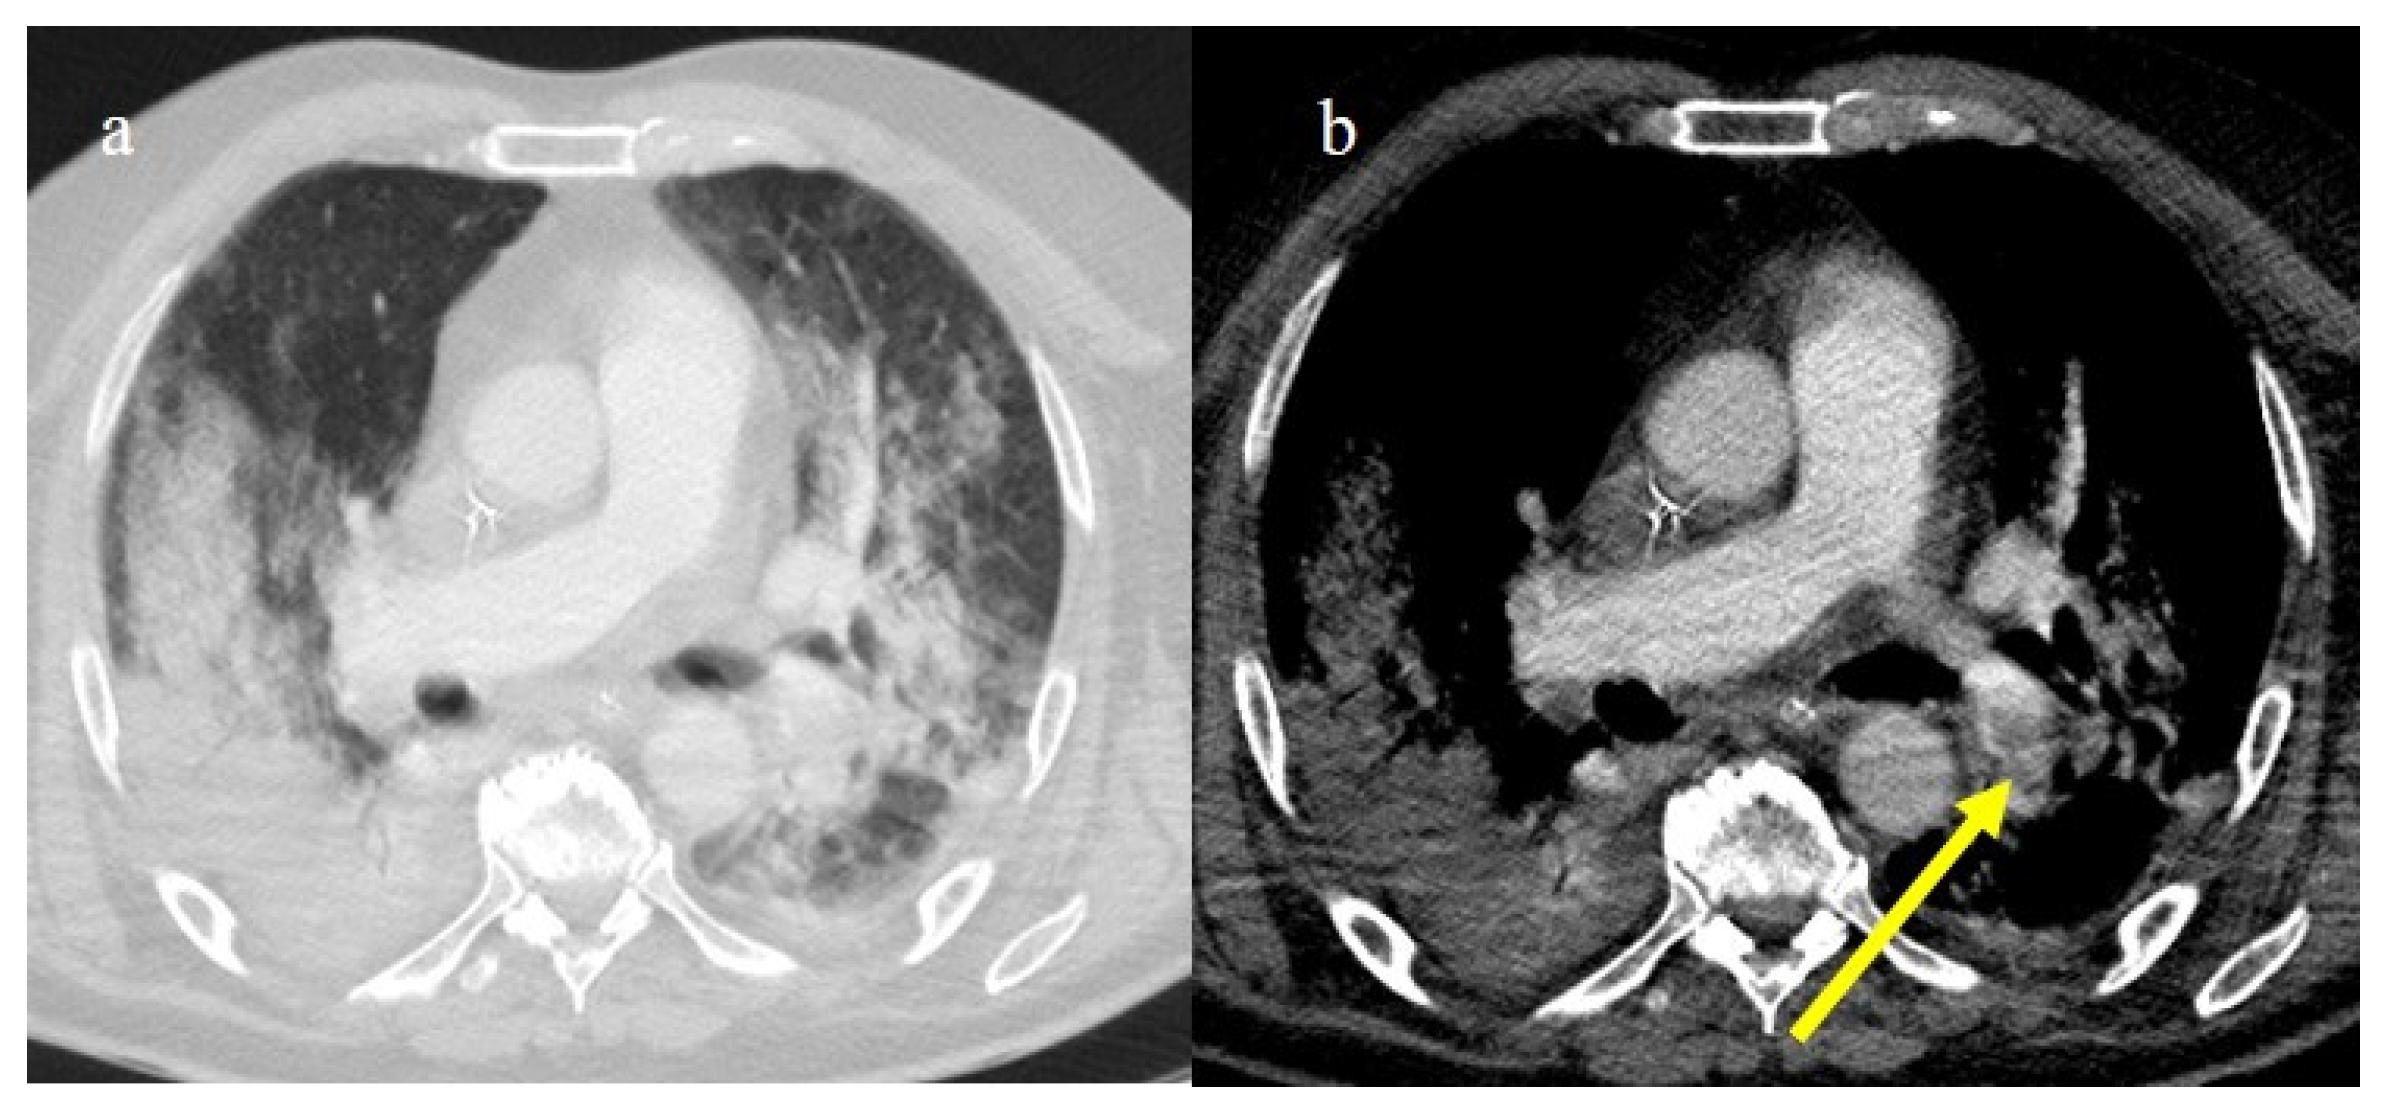

3.3.2. Pneumomediastinum and Pneumothorax

3.3.4. Pulmonary Thromboembolism